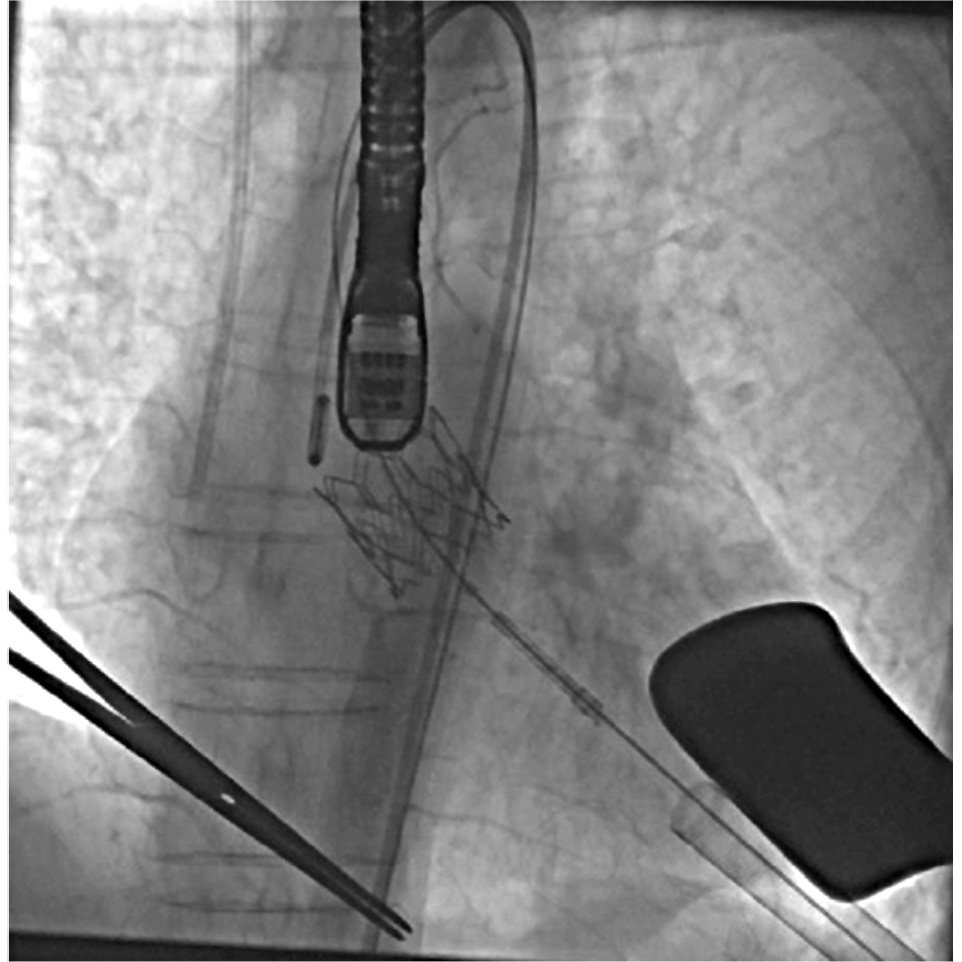

Выполнялась баллонная аортальная вальвулопластика. Далее через трансапикальную систему доставки протез устанавливался в позицию АоК. При высокочастотной стимуляции 200 уд./мин под контролем рентгеноскопии клапан имплантировался в позицию АоК (рис. 3). Корректность установки и работы клапана оценивалась на чреспищеводной ЭхоКГ. Непосредственно после имплантации клапана выполнялась коронарография для проверки проходимости коронарного русла.

Рис. 3. Рентгеноскопия имплантированного протеза в позицию аортального клапана.

Fig. 3. X-ray examination of the implanted prosthesis in the position of the aortic valve.